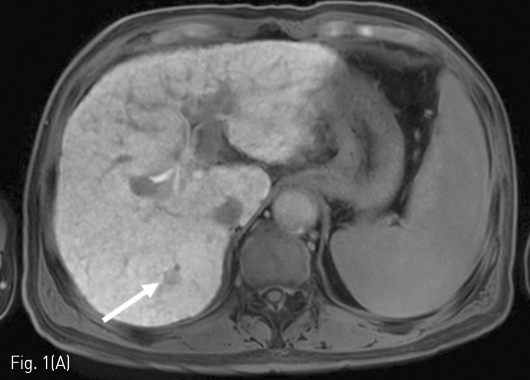

Massive arterioportal shunt after RFA. (A-B) A 1cm-sized tumor (arrow) was identified as low signal intensity on the hepatobiliary phase and high signal intensity on diffusion weighted imaging in the S7 of the liver.

Fig 1B

정기적 추적검사로 시행한 자기공명영상 (MRI)에서 7번 간분절(S7)에 간담도기에 저신호강도로 보이고 확산강조영상에서 고신호강도로 보이는 간암으로 의심되는 결절이 발견되어 고주파 열치료술이 시행되었다 (Fig. 1A, 1B). 10개월 후 추적검사로 시행한 전산화 단층 촬영의 동맥기 영상에서 우측 후방 간문맥이 주위 간동맥만큼 조영증강이 되는 소견을 보이고 있다(Fig. 1C, 1D). 동맥기 영상에서 간동맥과 간문맥 사이에 연결성이 보여 간동문맥단락이 의심되는 소견을 보이고 있다(Fig. 2).